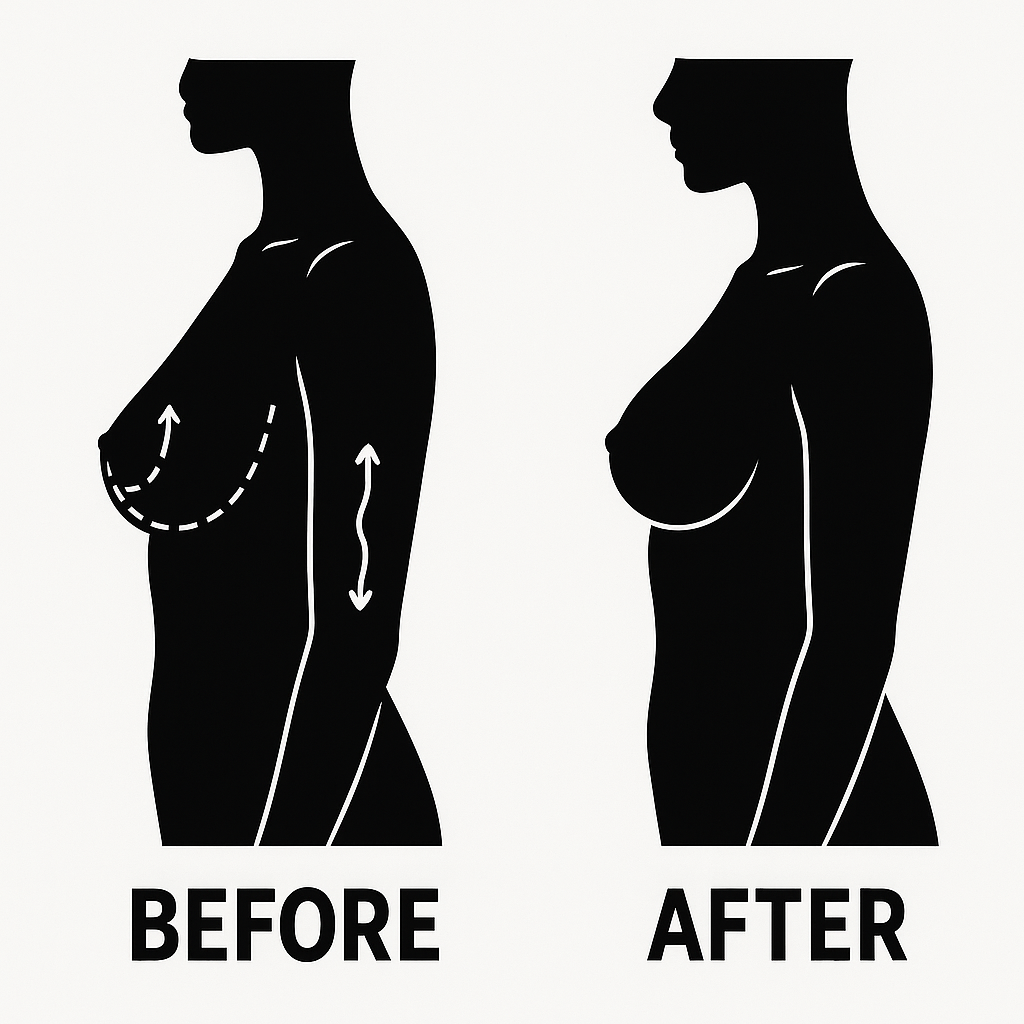

Breast Cancer Surgery & Care